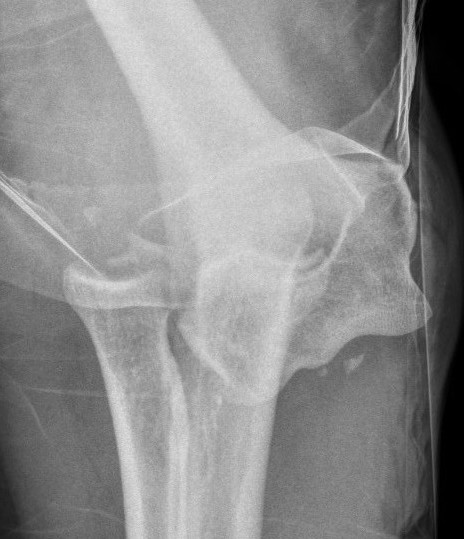

Elbow Dislocation Large Coronoid Fragment

Coronoid process

Complex Elbow Dislocation APComplex Elbow Dislocation Lateralelbo dis